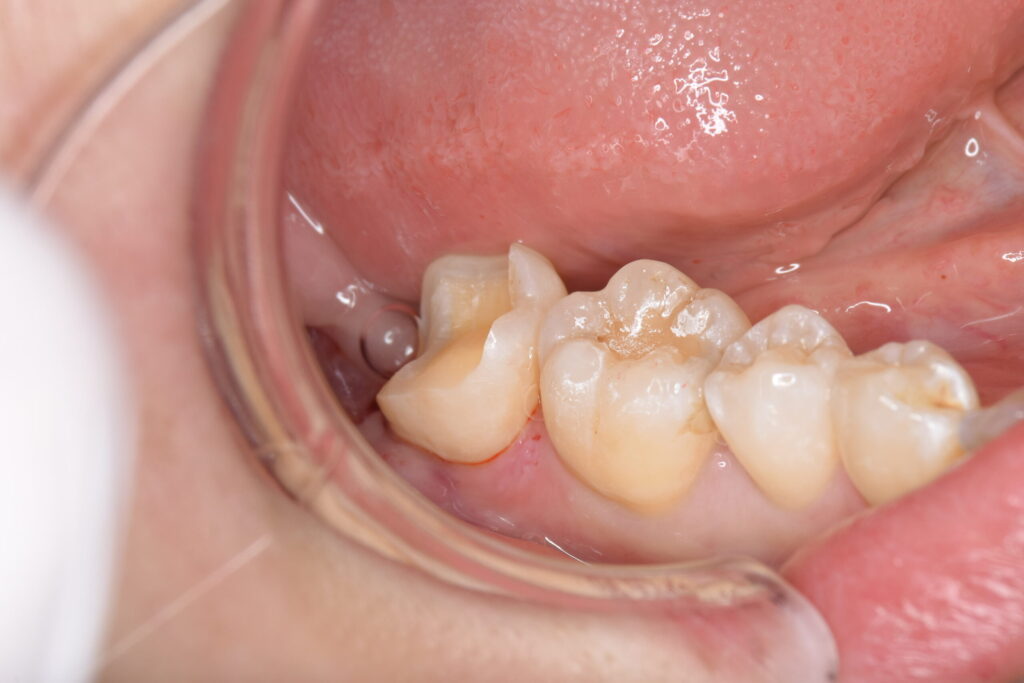

形成後の写真です。これから型取りをする所ですが、歯が半分以上残っていることがお分かりいただけると思います。

オーバーレイ(テーブルトップベニヤ)は、通常のセラミックの被せ物と比べ歯を削る量が圧倒的に少ないため、歯が痛む確率を下げることができます。

印象後、接着力を増す処置のためにラバーダム防湿下でCRコーティングを行っていきます。